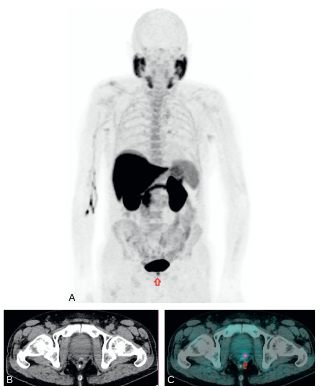

- la TEP aux analogues de l’antigène membranaire spécifique de la prostate (PSMA) est indiquée chez les patients présentant une récidive biologique lorsque la TEP à la 18FCH est négative (figure 30.6).

Fig. 30.6 TEP-TDM au 68Ga-PSMA. MIP 3D et coupe axiales TEP, TDM et TEP-TDM centrées sur le pelvis.

Patient présentant une récidive biologique dans un contexte d’adénocarcinome prostatique traité par prostatectomie deux ans auparavant. Images mettant en évidence une hyperfixation pathologique d’un ganglion obturateur gauche, suspecte de récidive isolée.

Source : CERF, CNEBMN, 2022.